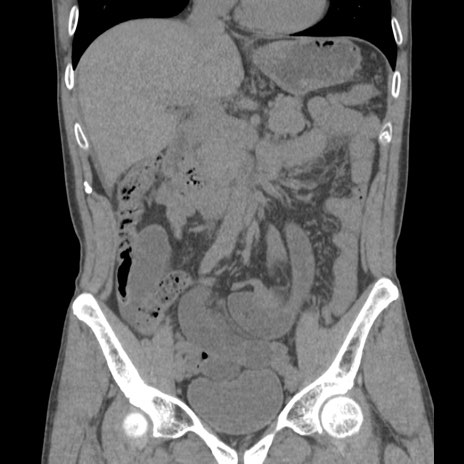

症例56 CT(冠状断像)

横断像